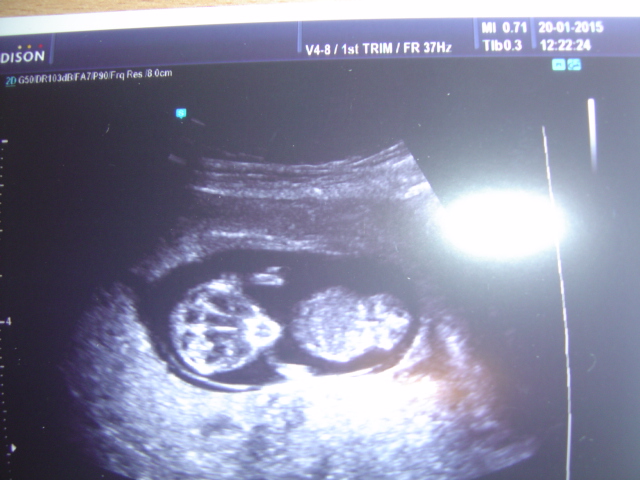

take prikladam fotecku manzel jak na ni koukal tak rikal ,ze je jak malej IT tak jsem se smala